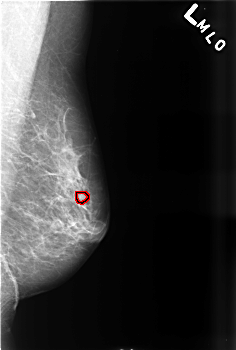

B_3471_1.LEFT_CC

LEFT_CC LINES 4488 PIXELS_PER_LINE 3008 BITS_PER_PIXEL 12 RESOLUTION 50 OVERLAY

FILE: B_3471_1.LEFT_CC.OVERLAY

TOTAL_ABNORMALITIES 1

ABNORMALITY 1

LESION_TYPE CALCIFICATION TYPE PUNCTATE DISTRIBUTION CLUSTERED

LESION_TYPE MASS SHAPE ROUND MARGINS MICROLOBULATED

ASSESSMENT 4

SUBTLETY 3

PATHOLOGY BENIGN

TOTAL_OUTLINES 1

BOUNDARY